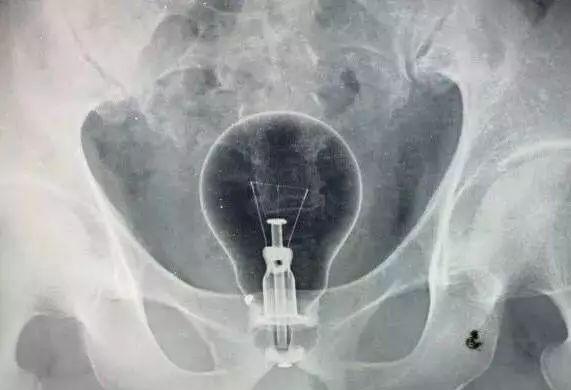

最近急诊科住了一名患者,因为直肠内异物被收治入院。直肠异物并不算什么罕见的事情,只不过这次的异物有点特殊:是个灯泡。

患者是个四十多岁的男性,由于各种原因,不慎将灯泡塞入体内无法取出。后因担心灯泡在体内破裂,故来就医。